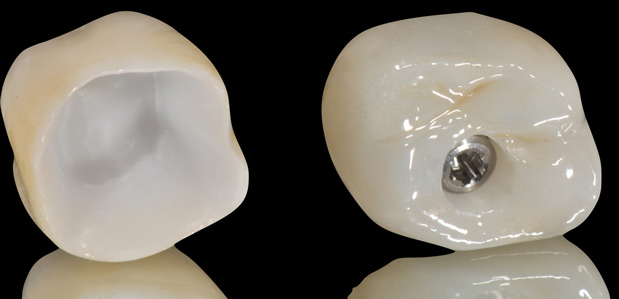

Fig 24. Full-contour monolithic crowns for teeth and implants constitute the last phase of the digital workflow.

Figure 24

Unfortunately, randomized clinical trials for fully digitalized workflows for either teeth or implant-supported fixed restorations are scarce. Presently, a strong offering of rapid prototyping procedures exists, including CAD/CAM-produced full-contour or monolithic crowns (Figure 24) and milled frameworks combined with CAD/CAM veneering superstructures. A true digital workflow for crown-and-bridge is not mainstage at present, and barely exists in an analog-digital blend, but the authors believe this will change soon. The layering of porcelain is cumbersome and operator dependent with many working parts and lacks the consistent precision found with today's computerized technology. Joda described a threefold improvement in time efficiency, and either no or minor adjustments of implant-supported crowns, using a digital workflow (intraoral scanning and CAD/CAM technology) in comparison to conventional methods.20 Laboratory time savings have been most impacted by the digital workflow (average 54.5 minutes of production time versus 132.5 minutes), along with a 30% overall treatment cost reduction.21